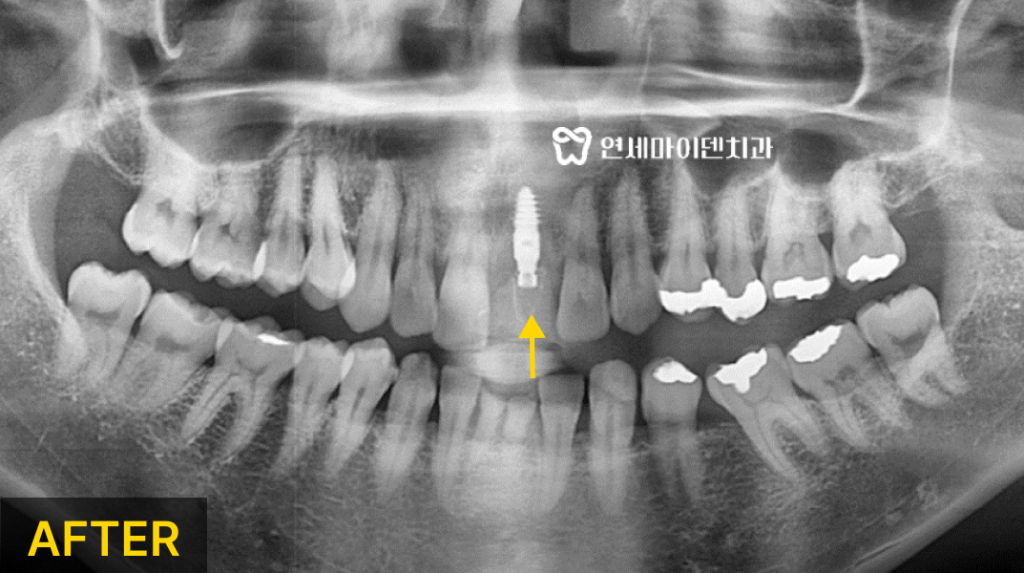

치아와 뼈가 재생되지 않고 염증이 점점 심해져 주변치아의 예후까지 위협할 수 있습니다.따라서 해당 치아는 발치 즉시 임플란트를 진행하기로 하였습니다.

임플란트 식립 시에는 임플란트를 식립할 위치와 각도가 매우 중요합니다.

수술 전 환자분과 상의 후 3D 네비게이션으로 모의 수술을 통해

임플란트를 식립할 위치를 정확히 설정했습니다.또, 발치 직후에는 기존에 있던 염증들을 깨끗하게 제거해야만

미세현미경을 통한 염증의 제거와 3D 네비게이션을 활용하여

발치 즉시 임플란트 식립을 진행하였습니다.식립 이후 잇몸 뼈가 잘 회복되는 것을 확인한 뒤

2차 임플란트 수술 후 최종 보철물까지 올려 치료를 마무리 했습니다.임플란트 수술 전, 고려해봐야 하는 것들